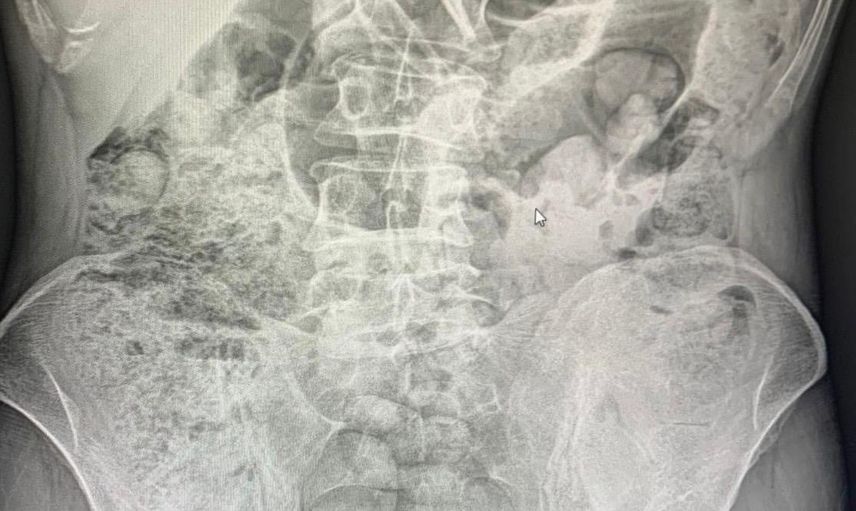

Siirt'te 4 zanlının midesinden çıkarılan 1 kilo 597 gram uyuşturucu madde, 10 gün süren hastane tedavisinin ardından cerrahi müdahale ile elde edildi. Tutuklanan zanlılar arasında 3 İran uyruklu kadın ve 1 erkek bulunuyor.

Siirt Emniyet Müdürlüğü Narkotik Suçlarla Mücadele Şube Müdürlüğü, 14 Aralık'ta Baykan Şehit Bünyamin Torgut Polis Uygulama Noktası'nda durdurduğu iki araçta, uyuşturucu madde taşımak için yutma yöntemini kullanan kişileri yakaladı. Yapılan incelemeler sonrasında, şüpheli şahısların midelerindeki uyuşturucu maddeler, 10 gün süren hastane süreci sonunda cerrahi yöntemle çıkarıldı.

Cerrahi Müdahale ile Elde Edilen Uyuşturucu

Midelerde toplamda 119 paket halinde 1 kilo 597 gram uyuşturucu madde tespit edildi. Zanlılar, çıkarıldıkları adli makamlarca tutuklanarak cezaevine gönderildi.

SİİRT’TE 4 ZANLININ MİDELERİNDEKİ 1 KİLO 597 GRAM UYUŞTURUCU MADDE, 10 GÜNLÜK HASTANE SÜRECİNİN ARDINDAN CERRAHİ MÜDAHALEYLE ÇIKARTILDIKTAN SONRA TUTUKLANDI.